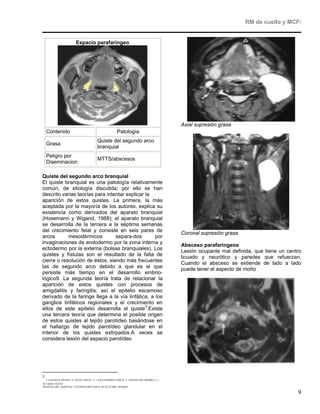

Programación de AX de MCF                          Patología de cuello Suprahioidea

En este caso será paralelos a paladar duro desde

senos frontales hasta el borde inferior de la                  Espacio mucoso faríngeo

mandíbula

Programación de COR de MCF

El paquete de cortes se perpendicular al paladar

nasofaringe, hiperintensa en secuencia T2 y de

duro desde cartílago nasal hasta la columna

intensidad intermedia en T1 (variable según la

vertebral